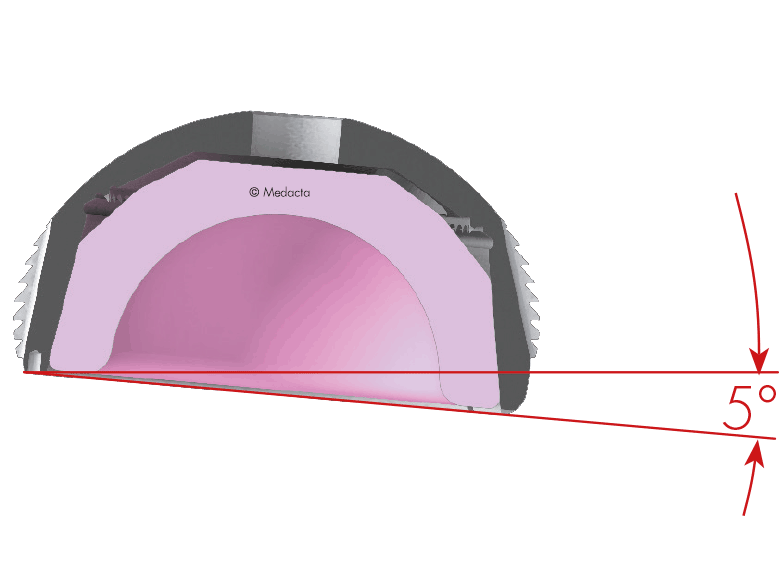

ACETABULAR COMPONENT

The acetabular component is the part of the implant that replaces the socket of your hip joint. It typically consists of a titanium shell that fits into the pelvis, and a smooth inner liner made of either ceramic or highly cross-linked polyethylene.

To help personalise your procedure, your surgeon will use MyHip, an advanced digital planning platform that creates a 3D model of your hip based on your CT scans and X-rays. This allows for highly tailored pre-operative planning.

With MyHip, your surgical team can virtually select and position the implant to match your anatomy, assess your joint alignment, and plan for optimal leg length and offset. This level of precision aims to support better alignment, smoother joint mechanics, and a more natural-feeling hip replacement.

Where appropriate, custom 3D-printed surgical guides may be created to match your anatomy precisely. These instruments are designed to help your surgeon carry out the planned procedure in theatre with a high level of accuracy.

These guides can be used with both anterior and posterior surgical approaches and are selected based on what is most appropriate for your individual case. This technology supports surgical precision and may contribute to improved function and long-term outcomes.